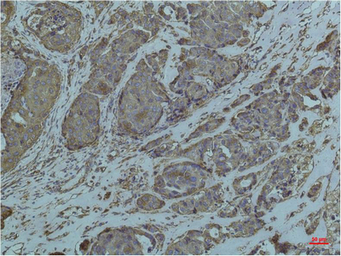

IHC-P analysis of human breast carcicnoma tissue using GTX33997 Grp78 antibody [10C9].

Dilution : 1:200